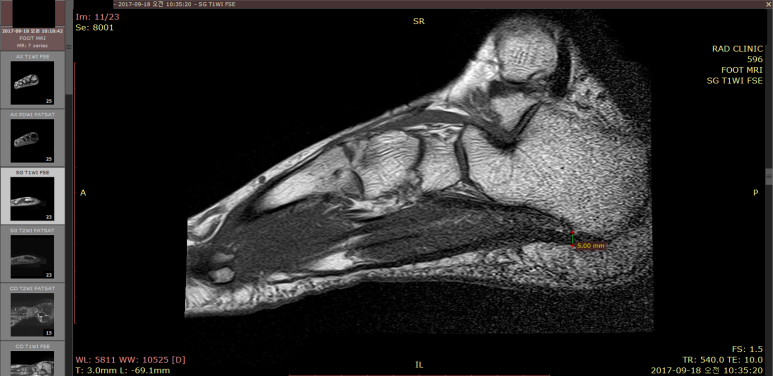

이 환자분은 아픈지워낙 오래되어

발바닥 근막 이외에 주변 힘줄, 인대, 관절의 다른 문제가 없는지 확인할 필요가 있어

협력병원 영상의학과에 MRI를 의뢰했습니다.

영상의학과 전문의 선생님께서 족저근막염으로 진단하셨고

이외에 다른 문제는 없다고 소견을 주셨습니다.

족저근막의 가장 두꺼운 부분을 측정해보니 무려 9mm가 나옵니다.

정상 3-4mm인데, 2배 이상 된 것이죠.

보통 족저근막염 환자들이 5mm 내외 인걸 감안하면 심각한 상태입니다.